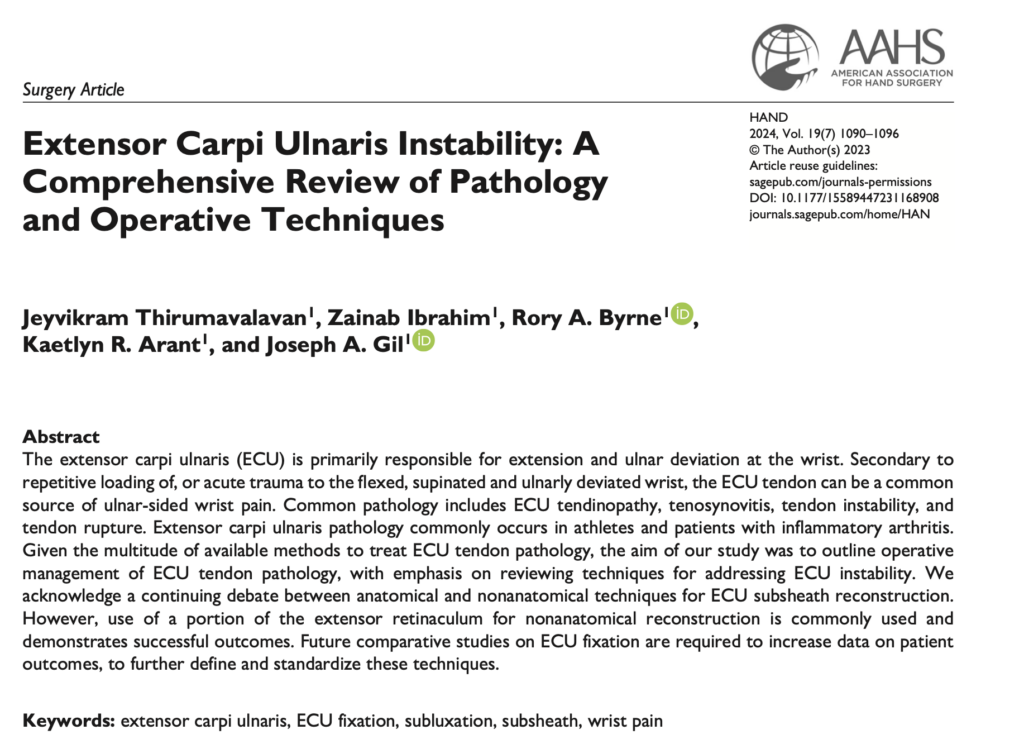

手首の尺側痛は原因がひとつではないことが多く、TFCC損傷、遠位橈尺関節の不安定性、腱鞘炎、腱の亜脱臼や脱臼などが複雑に絡み合っていることも少なくありません。今回ご紹介する論文では、ECU腱不安定症の病態と手術治療が体系的にまとめられており、尺側手関節痛を理解するうえで非常に重要な内容が示されています。

ECU腱は、手首を伸ばしたり、小指側へ動かしたりする働きをもつ重要な腱です。特に、手首をひねる動作、ラケットやゴルフクラブを振る動作、強く物を握って手首を固定する動作で大きな役割を果たします。論文では、ECU腱は手関節の尺側にある第6コンパートメントを通り、専用のトンネルと腱鞘様構造(subsheath)によって安定化されていると整理されています。

さらに重要なのは、ECU腱の周囲の構造がTFCCや遠位橈尺関節の安定性とも深く関係していることです。つまり、ECU腱の問題とTFCC損傷は別々に存在するのではなく、相互に関連しながら手首の痛みを引き起こしている場合があります。

手首の小指側が痛いと、「TFCC損傷」という病名を耳にする方は多いと思います。もちろんTFCC損傷は非常に重要ですが、論文でも示されているように、ECU腱障害はTFCC、月状三角靱帯、遠位橈尺関節、尺骨茎状突起周囲の病変と併存しやすいことが大きなポイントです。

論文では、診断には丁寧な問診と身体所見が不可欠であり、そのうえで画像評価を組み合わせることが重要だと述べられています。

画像検査としては、X線、MRI、そして超音波検査が重要です。中でも超音波は、論文でも動的評価ができる、健側とその場で比較できる、非侵襲的でアクセスしやすいという点で大きな利点があるとされています。

これは臨床的にも非常に大きな意味があります。ECU腱の障害は、静止画像だけではわかりにくいことがあります。実際に前腕を回してもらいながら腱の動きを観察できるエコーは、ECU腱不安定症の診断にきわめて有用です。

この論文の中心テーマは、ECU腱不安定症に対する手術法です。内容を簡単にまとめると、手術では主に破れたsubsheathの修復、あるいは伸筋支帯を使った再建が行われます。

論文では、解剖学的修復と非解剖学的再建の両方が紹介されていますが、伸筋支帯の一部を用いた再建は広く行われ、良好な成績が報告されているとされています。

さらに注目すべき点として、論文ではTFCC損傷が疑われる場合には手関節鏡が診断と治療の両面で有用であると述べています。